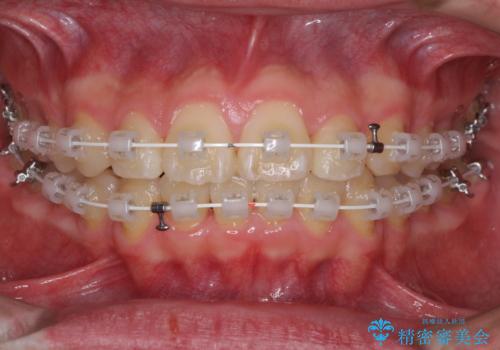

- 矯正装置

- 審美装置

中学生と言うこともあり、1年強の短期間で終了しました。